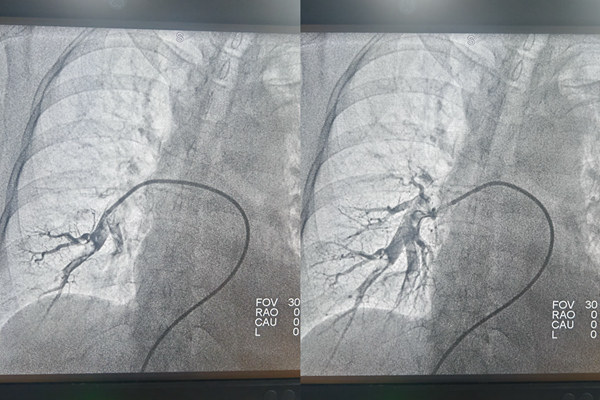

手術(shù)前后肺動(dòng)脈造影對(duì)比。重慶兩江新區(qū)人民醫(yī)院供圖

隨后,通過導(dǎo)管抽吸出血栓,疏通“堵點(diǎn)”,肺動(dòng)脈血流即刻恢復(fù)暢通。接下來解決左側(cè)骼靜脈重度狹窄問題。治療團(tuán)隊(duì)向左側(cè)骼靜脈送入細(xì)導(dǎo)絲,并沿導(dǎo)絲送入一個(gè)小小的球囊,將狹窄的血管擴(kuò)張開來,再于血管狹窄處放置一枚支架,支撐起狹窄的血管壁,使血流重新通暢。

手術(shù)歷時(shí)約一小時(shí),成功拆掉了張麗體內(nèi)的“不定時(shí)炸彈”,在醫(yī)護(hù)人員的精心的術(shù)后治療和護(hù)理下,張麗恢復(fù)良好,肺動(dòng)脈栓塞情況得到有效治療。